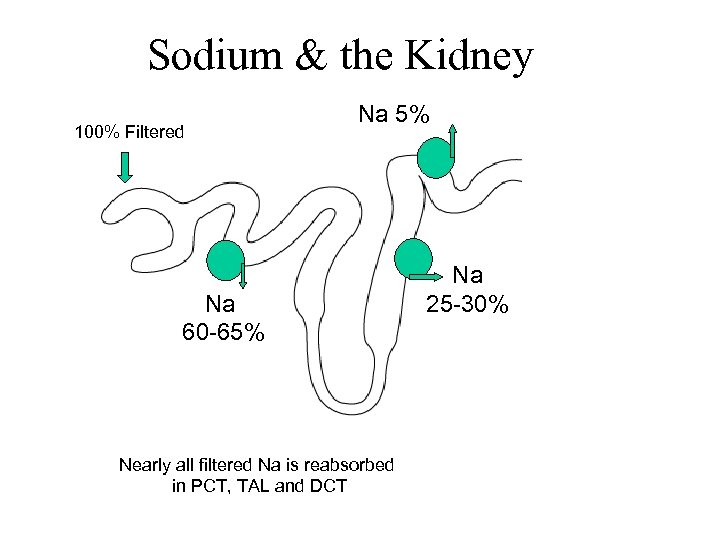

Sodium & the Kidney 100% Filtered Na 5% Na 60 -65% Nearly all filtered Na is reabsorbed in PCT, TAL and DCT Na 25 -30% Na 4% Day to day control of Na excretion takes place in CCD by aldo and ADH

Sodium & the Kidney 100% Filtered Na 5% Na 60 -65% Nearly all filtered Na is reabsorbed in PCT, TAL and DCT Na 25 -30% Na 4% Day to day control of Na excretion takes place in CCD by aldo and ADH

Sodium & the Kidney 100% Filtered Na 5% Na 60 -65% Nearly all filtered Na is reabsorbed in PCT, TAL and DCT Na 25 -30% Na 4% Day to day control of Na excretion takes place in CCD by aldosterone

Sodium & the Kidney 100% Filtered Na 5% Na 60 -65% Nearly all filtered Na is reabsorbed in PCT, TAL and DCT Na 25 -30% Na 4% Day to day control of Na excretion takes place in CCD by aldosterone